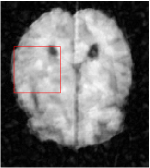

All the experiments are implemented on a Windows workstation with Intel Core i9 CPU at 3.3GHz and an Nvidia GTX-1080Ti GPU with 11GB of graphics card memory via TensorFlow Abadi et al. (2016). The parameters in the proposed network are initialized by using Xavier initialization Glorot and Bengio (2010). We trained the meta-learning network with four tasks synergistically associated with four different CS ratios: 10%, 20%, 30%, and 40%, and test the well-trained model on the testing dataset with the same masks of these four ratios. We have 300 training data for each CS ratio, which amount to total of 1200 images in the training dataset. The results for and MR reconstructions are shown in Tables 5.4 and 5.4 respectively. The associated reconstructed images are displayed in Figures 1 and 3. We also test the well-trained meta-learning model on unseen tasks with radio masks for skewed ratios: 15%, 25%, 35%, and random Cartesian masks with ratios 10%, 20%, 30% and 40%. The task-specific parameter for the unseen tasks are retrained for different masks with different sampling ratios individually with fixed task-invariant parameters . In this experiments, we only need to learn for three skewed CS ratios with radio mask and four regular CS ratios with Cartesian masks. The experimental training proceed on less data and iterations, where we performed on 100 MR images with 50 epochs. For example, for reconstructing MR images with CS ratio 15% radio mask, we fix the parameter and retrain the task-specific parameter on 100 raw data with 50 epochs, then test with renewed on our testing data set with raw measurement that sampled from radio mask with CS ratio 15%. The results associated with radio masks are shown in Table 5.4 and 5.4, Figure 2 and 4 for and images respectively. The results associated with Cartesian masks are list in Table 5.4 and reconstructed images are displayed in Figure 5.

Qualitative comparison between conventional and Meta-learning methods are shown in Figure 1 and 3, which display the reconstructed MR images of the same slice for T1 and T2 respectively, we label the zoomed-in details of HGG in the red boxes. We observe the evidence that conventional learning is more blurry and lost sharp edges, especially in lower CS ratios. From the point-wise error map, we find meta-learning has the ability to reduce noises especially in some detailed and complicated regions comparing to conventional learning.

In this section, we test the generalizability of the proposed model that tests on unseen tasks. We fix the well-trained task-invariant parameter and only train for sampling ratios 15%, 25% and 35% with radio masks and sampling ratios 10%, 20%, 30% and 40% with Cartesian masks. In this experiment, we only used 100 training data for each CS ratio and apply a total of 50 epochs. The averaged evaluation values and standard deviations are listed in Table 5.4 and 5.4 for reconstructed T1 and T2 brain images respectively that proceed with radio masks, and Table 5.4 shows the qualitative performance for reconstructed T2 brain image that applied random Cartesian sampling masks. In T1 image reconstruction results, meta-learning improved 1.6921 dB in PSNR for 15% CS ratio, 1.6608 dB for 25% CS ratio, and 0.5764 dB for 35% comparing to the conventional method, which in the tendency that the level of reconstruction quality for lower CS ratios improved more than higher CS ratios. A similar trend happens in T2 reconstruction results with different sampling masks. The qualitative comparisons are illustrated in Figure 2, 4 and 5 for T1 and T2 images tested in skewed CS ratios in radio masks, and T2 images tested in Cartesian masks with regular CS ratios respectively. In the experiments that conducted with radio masks, meta-learning is superior to conventional learning especially at CS ratio 15%, one can observe that the detailed region in red boxes keeps edges and is more close to the true image, while conventional method reconstructions are hazier and lost details in some complicated tissue. The point-wise error map also indicates that Meta-learning has the ability to suppress noises.

Training with Cartesian masks is more difficult than radio masks, especially for conventional learning where the network is not very deep since the network only applied three convolutions each with four kernels. Table 5.4 indicates that the average performance of meta-learning improved about 1.87 dB comparing to conventional methods with T2 brain images. These results further demonstrate that meta-learning has the benefit of parameter efficiency, the performance is much better than conventional learning even if we apply a shallow network with small size of training data.